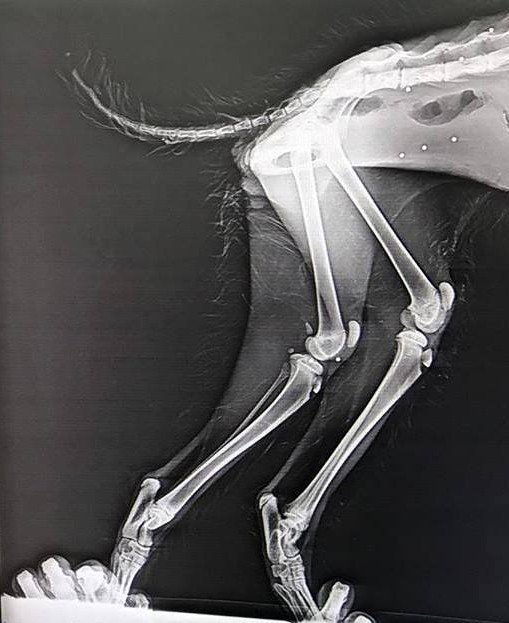

Genç ilçesi Soğuksu köyünde duyarlı vatandaşlar tarafından arazide fark edilen vaşak, Bingöl Doğa Koruma Milli Parklar Müdürlüğü aracılığıyla Kars Kafkas Üniversitesi Yaban Hayatı Kurtarma ve Rehabilitasyon Merkezine getirildi. Vücudunda saçmaların isabet ettiği belirlenen yaralı vaşak ameliyata alındı.

Vaşağın, Rehabilitasyon Merkezindeki muayenesinde çekilen röntgenlerde vücudunun çeşitli yerlerinde saçma taneleri bulunduğu tespit edildi. Gerekli tedavi ve rehabilitasyon işlemlerinin tamamlanmasının ardından vaşak, doğal ortamına bırakılacak.